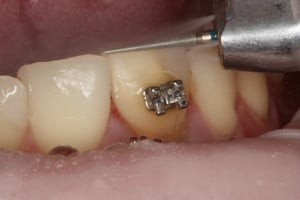

Przykład ekstruzji ortodontycznej za pomocą płytki termoformowalnej i zameczka ortodontycznego: